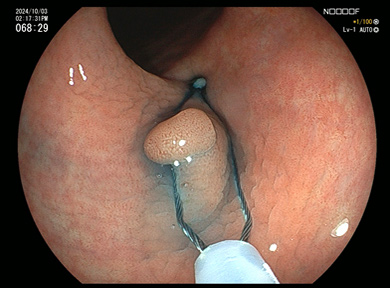

大腸ポリープ

通常光(白色光)

通常光では淡い発赤ですが

特殊光-1

同じところを空気量調整し特殊光LCIにて観察

特殊-2

同じところを特殊光BLIにて血管と表面構造を観察

ポリープ切除術

1

IS型といわれる大腸ポリープです。

2

スネアをポリープに引っ掛けます。

3

スネアの輪を絞ります。

4

ポリープを切除、血液のにじみはわずかです。